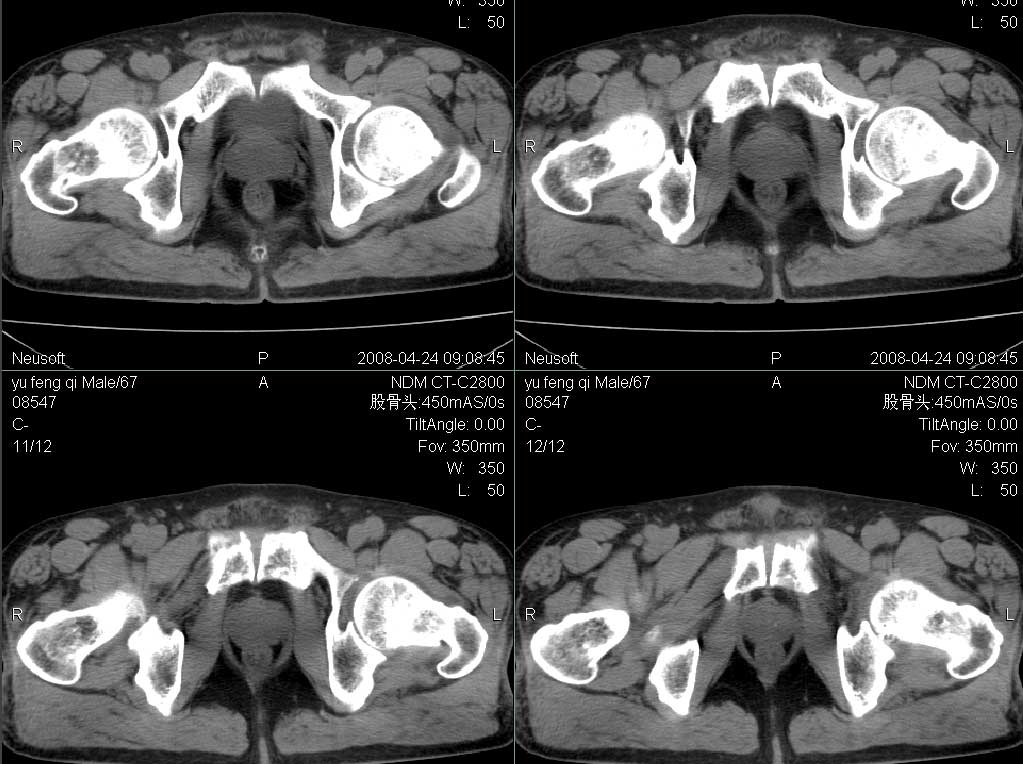

标题: CT13069:双髋关节 [打印本页]

标题: CT13069:双髋关节

男67岁,左髋疼痛破行2月。

左侧髋关节积液,无菌坏死待排,建议mri检查

建议行mri检查排除左侧股骨头无菌性坏死。

左髋关节积液,建议mr检查。

支持左侧髋关节少量积液.

支持双款关节轻度退变,左髋关节少许积液

ct平扫未见明显异常,建议行mri检查排除左侧股骨头无菌性坏死早期改变。

其它退行性改变。